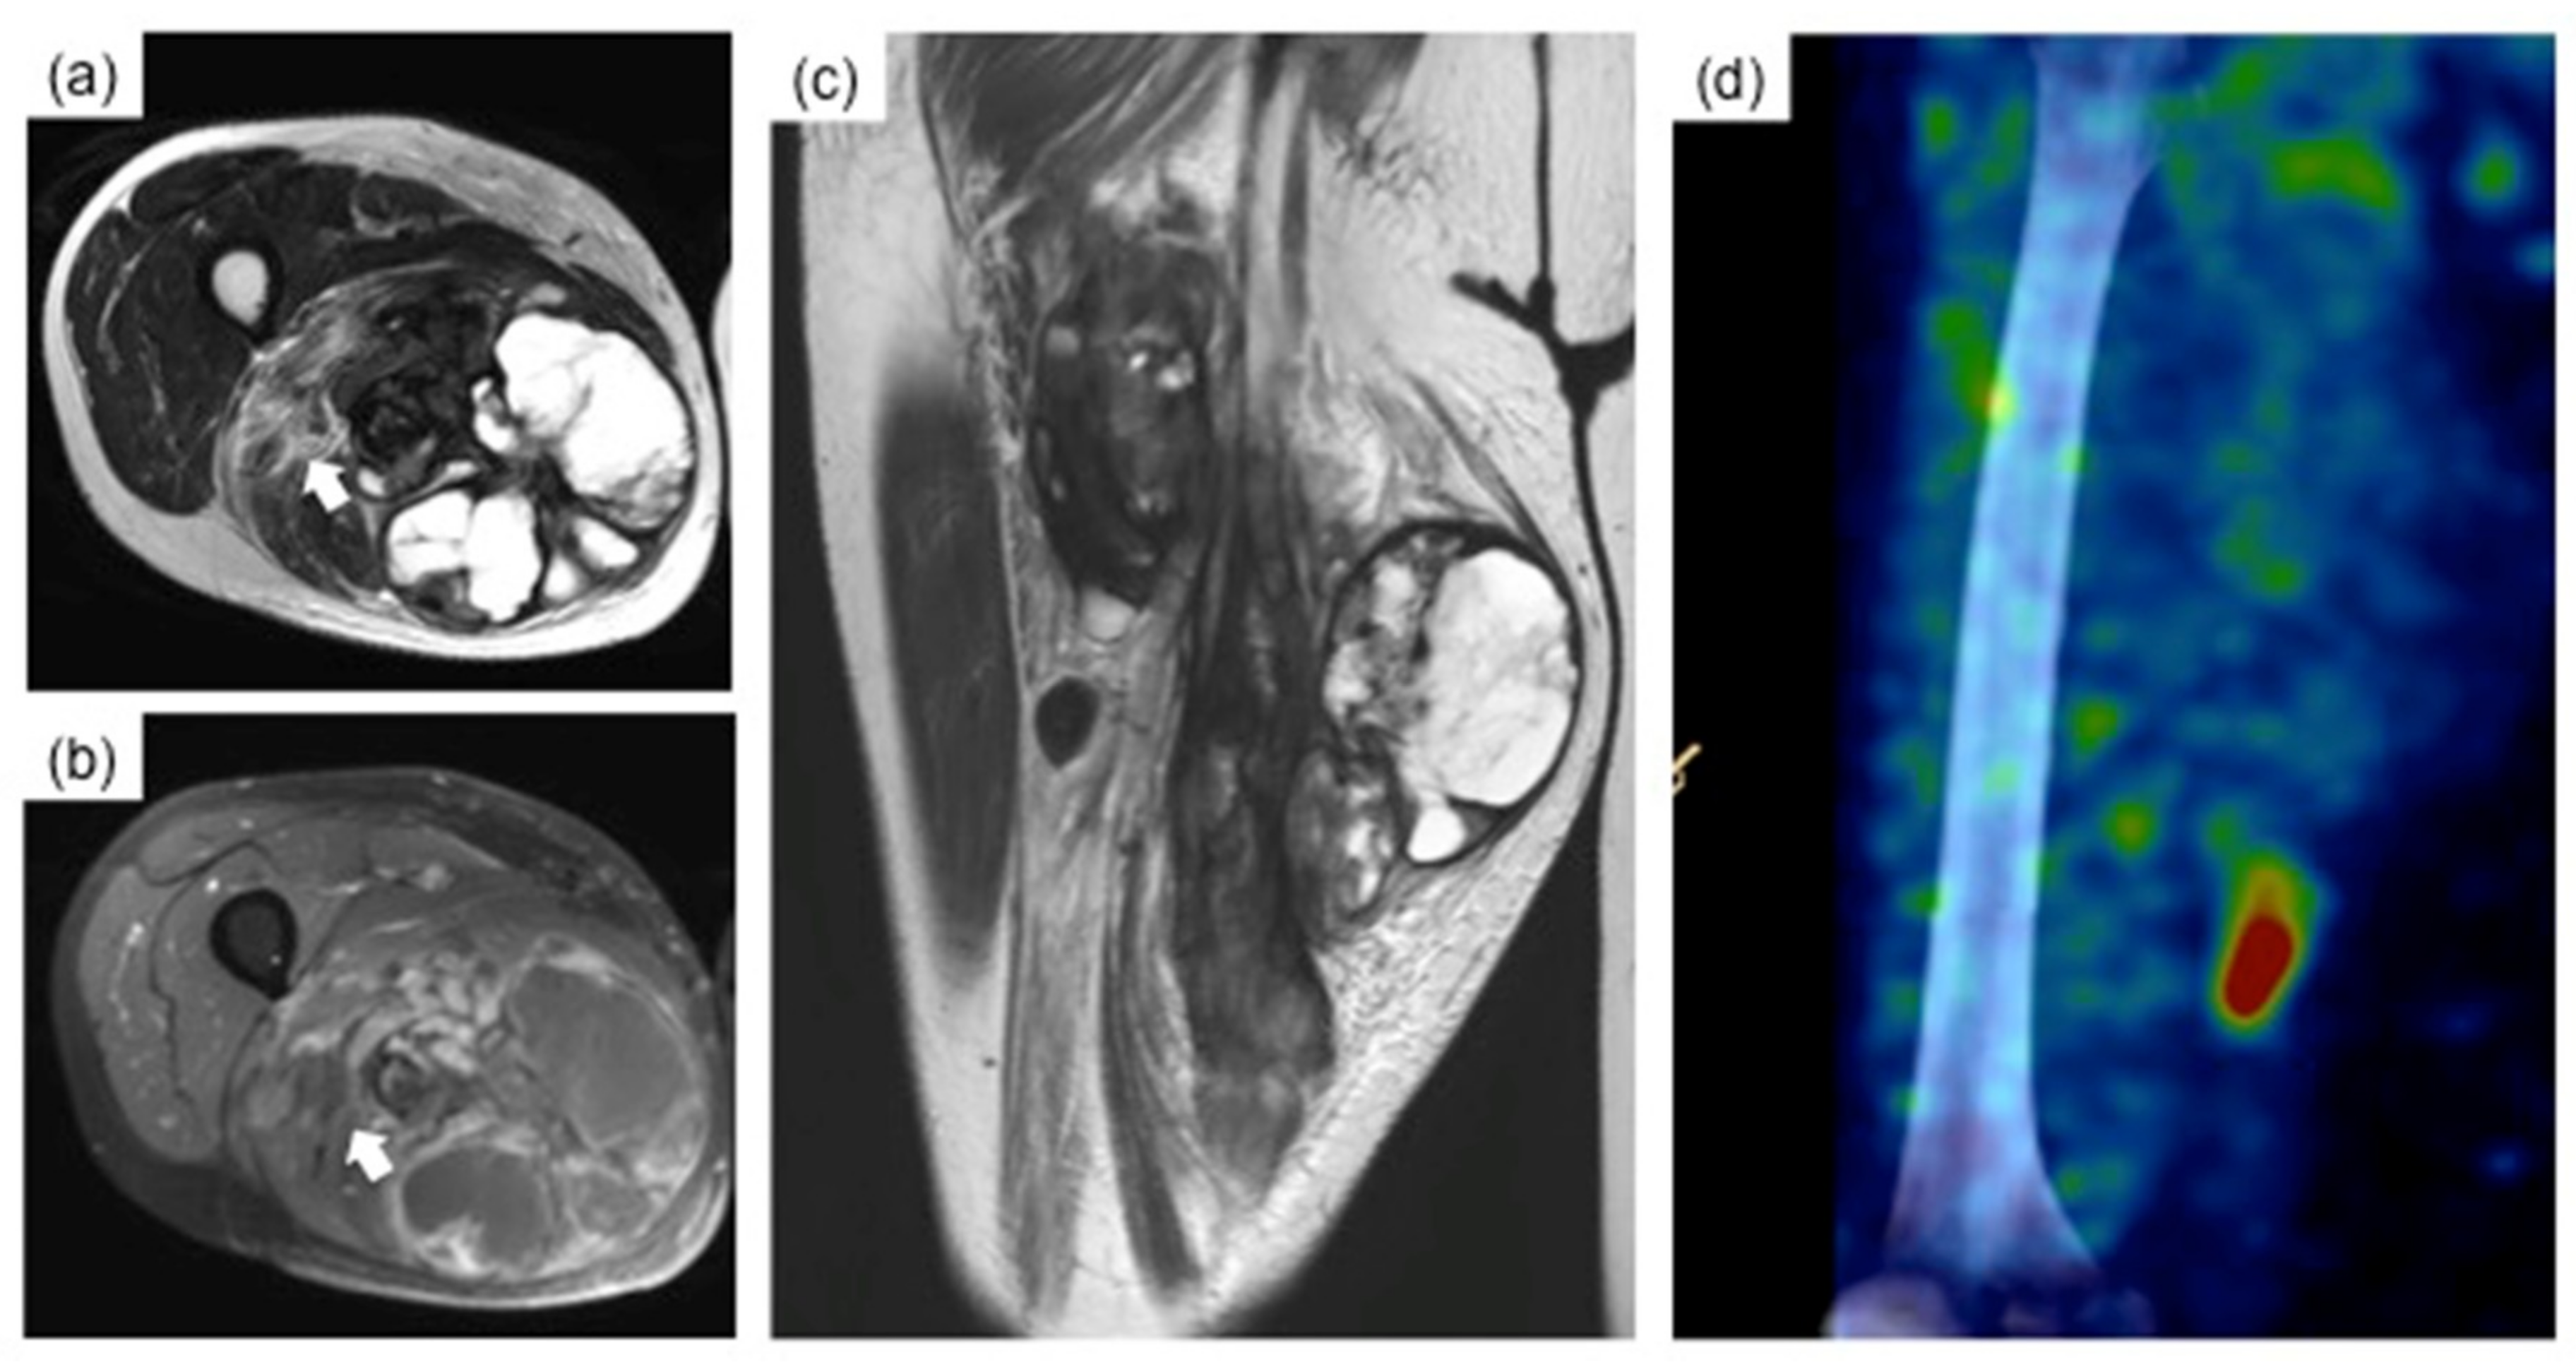

2. Case Presentation

3. Surgical Procedure

4. Postoperative Course